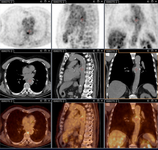

Q fever aortic mycotic lumbar aneurysm diagnosed at PET scan: 18F-fluorodeoxyglucose PET/CT. In this asymptomatic patient with heart valve history with elevated serology, the PET scan diagnosed an aortic endocarditis on native valve with thoracic and lumbar aortic mycotic aneurysms

Institut Hospitalo-Universitaire Méditerranée Infection (patient consent obtained)

Q fever aortic mycotic thoracic aneurysm diagnosed at PET scan: 18F-fluorodeoxyglucose PET/CT. In this asymptomatic patient with heart valve history with elevated serology, the PET scan diagnosed an aortic endocarditis on native valve with thoracic and lumbar aortic mycotic aneurysms

Q fever endocarditis diagnosed at PET scan: 18F-fluorodeoxyglucose PET/CT. In this asymptomatic patient with heart valve history with elevated serology, the PET scan diagnosed an aortic endocarditis on native valve with thoracic and lumbar aortic mycotic aneurysms